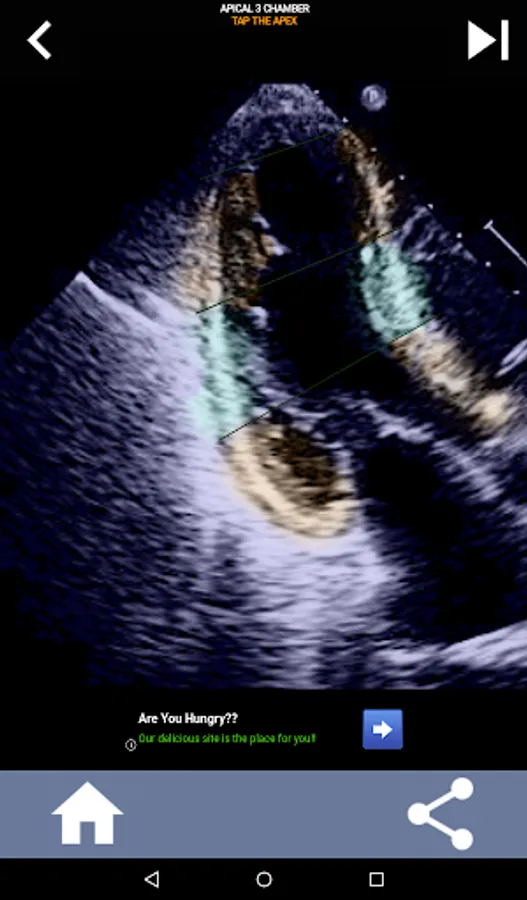

Understanding the AHA (American Heart Association) heart segments is of utmost importance for a cardiac sonographer to effectively communicate with the cardiologist who writes the report. By knowing the specific anatomical regions and their corresponding segments, the sonographer can accurately describe and communicate any abnormalities or findings, ensuring clear and concise communication between both professionals.

This understanding becomes particularly crucial when the cardiologist seeks to ascertain the precise location of a problem or when the on-call physician identifies an issue within a specific region, prompting the sonographer to accurately display the corresponding segment, such as the mid-inferior wall. Thus, possessing a comprehensive grasp of the AHA heart segments is essential skill set.

This app will test your knowlegde using actual echo images, which I often find to be the best teaching method.